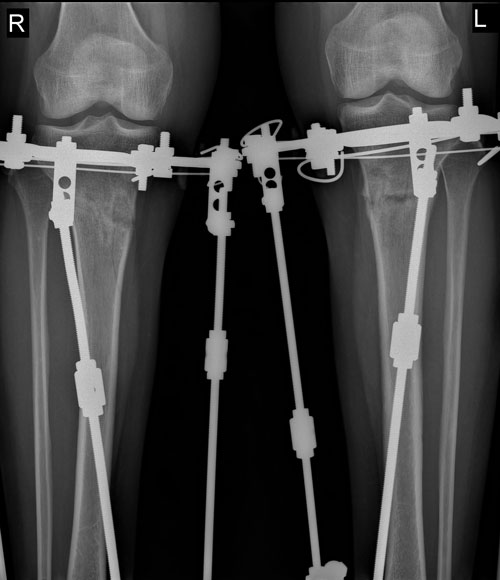

Добрый вечер форумчане-ониповцы! У меня сегодня 76 дней-2,5 месяца.

Пораньше ехать снимать не рискнула-лучше до 90дн.дотяну. Хотя с приближением заветных дней не терпится пролистать календарь побыстрее. Стала замечать, что я оказывается уже встаю и сажусь без опоры. То есть шаг за шагом возвращаюсь к обычной жизни. И ходить намного легче стало. Сегодня первый раз за столько месяцев села за руль сама-я так соскучилась по своей машинке красавице-и поехала в супермаркет за продуктами. У нас у всех одна цель, но дорогами идем разными---кто то быстро добегает, кто то, как я, потихонечку. После операции я думала, что я сильная и быстро войду в колею. Но не тут то было. И по лестнице я только начала подниматься двумя ногами попеременно, как положено, а не одной бочком. Так что терпение, товарищи!